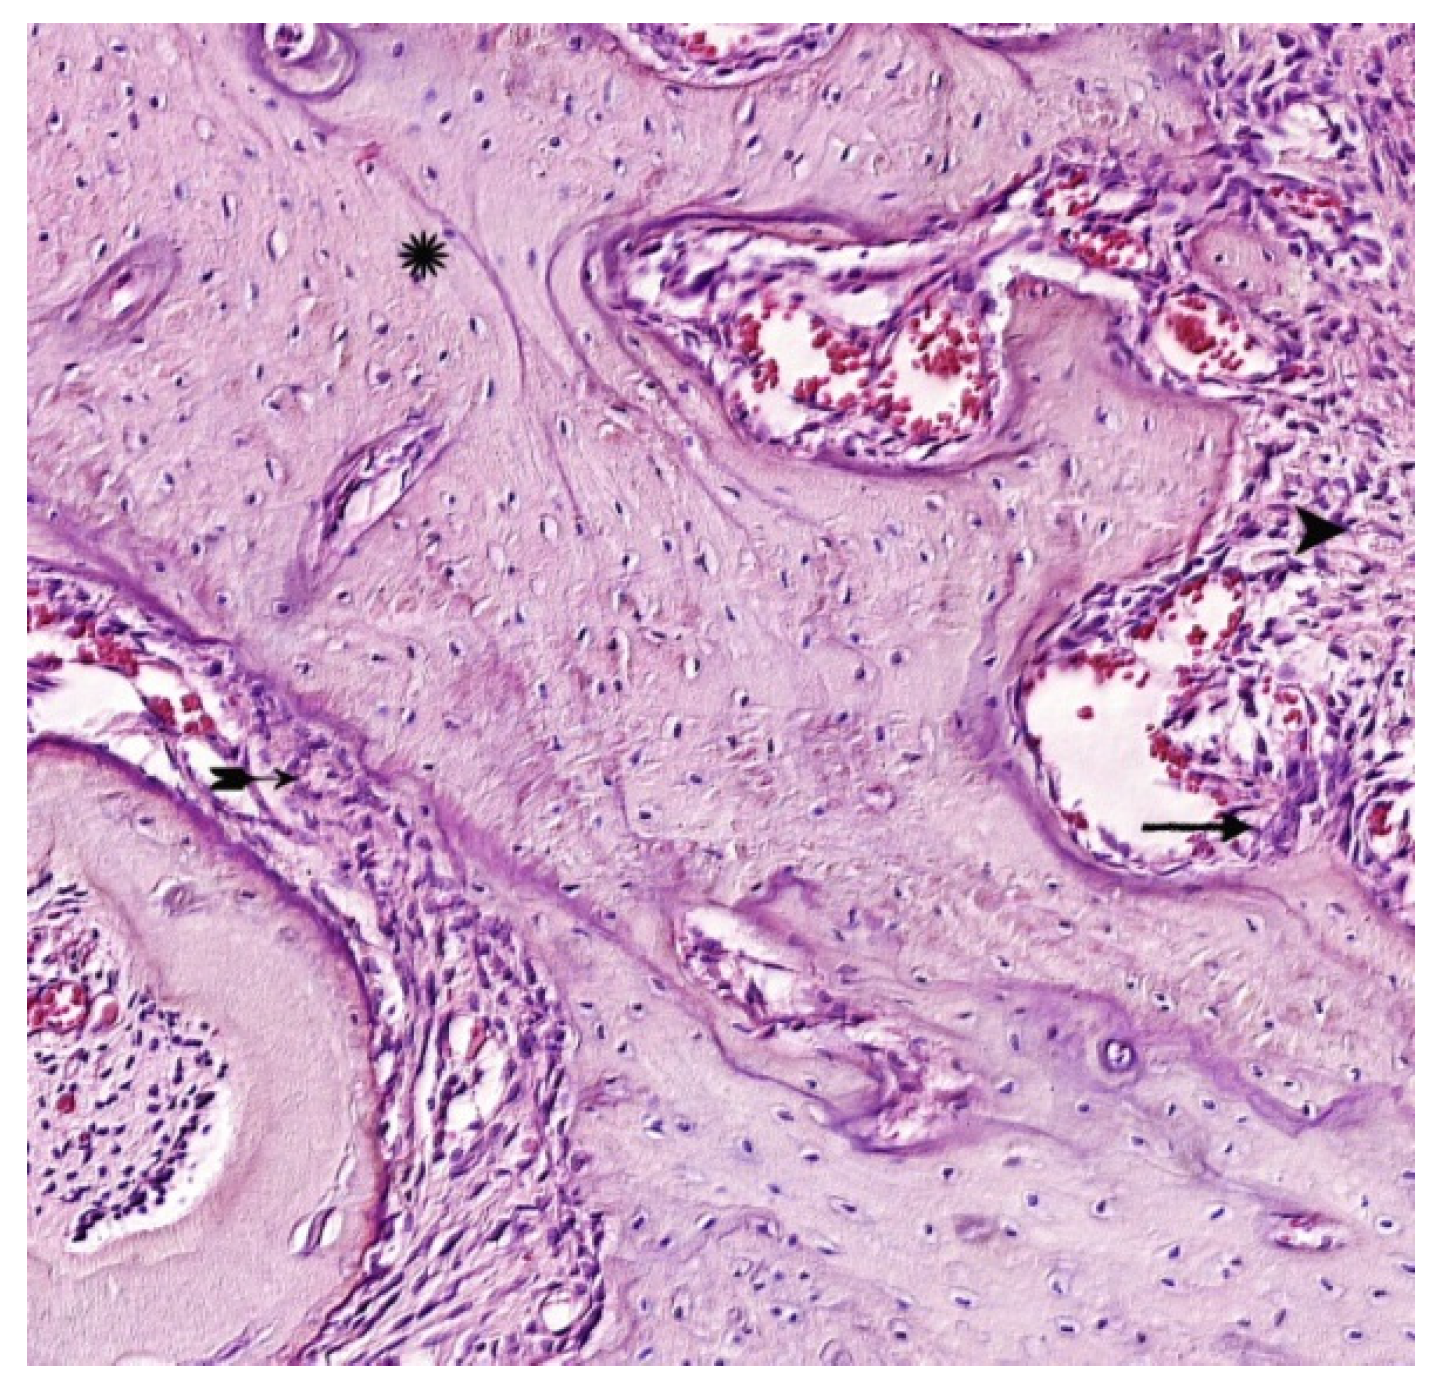

). Hematoxylin-eosin staining. Magnification x400.